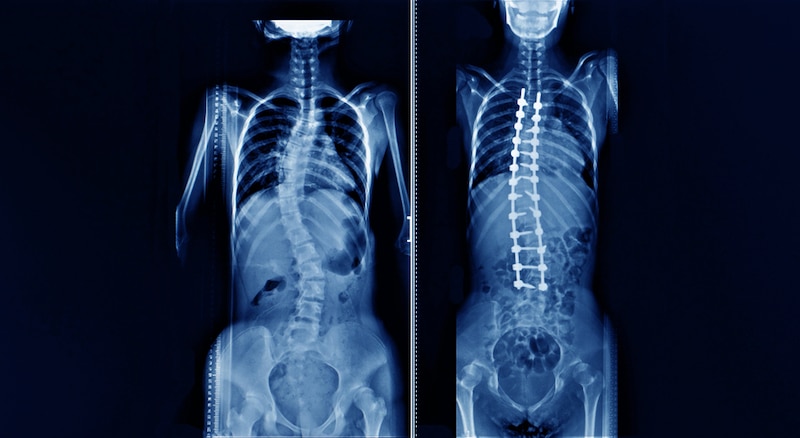

Scoliosis is characterized by an abnormal curvature of the cervical spine, often forming an “S” or “C” shape when viewed from the front or back. While the exact cause of scoliosis may vary, it can be classified into different types, including: